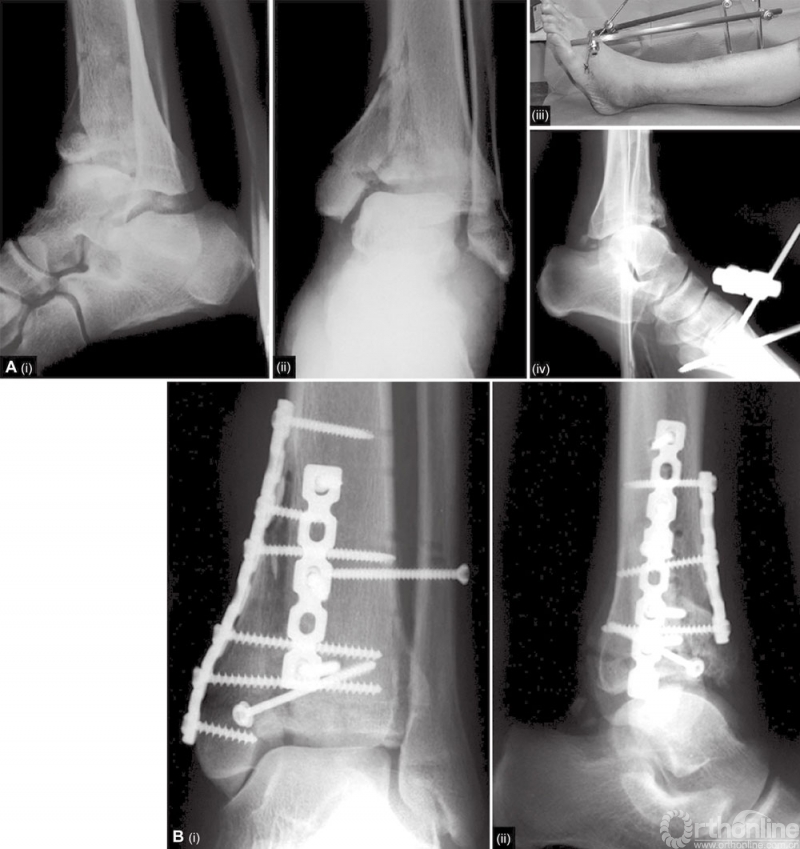

主要的软骨缺损必须要用骨移植物进行填充。移植骨的金标准仍然是来自髂嵴的自体骨移植。有时需要用皮质海绵骨移植支撑明显的骨缺损。钢板最终用来固定Pilon骨折。在Ⅰ、Ⅱ型骨折中,支撑钢板的轮廓贴合胫骨远端的内侧面就足够了。3.5 DCP或低切迹钢板放置到胫骨的内侧面(图8)。如果骨折向近端延伸,一个微创经皮固定技术在骨干是可行的。三叶接骨板覆盖骨面较大,可能会阻碍血运。

图8 A和B B型骨折用重建板和拉力螺钉进行固定

如果内侧钢板不足以稳定骨折,应用两个支撑,一个在内侧,一个在外侧。相比较于各种设计的胫骨远端板,无论是锁定的还是非锁定的,两个重建板可以提供更多的稳定性。伤口闭合前止血带应当释放,使筋膜处于开放状态。放置一到两个引流管。皮肤用无创技术进行无张力缝合。如果腓骨同时被修复,因张力问题可以使腓骨伤口敞开,并用无菌敷料(如聚氨酯泡沫)覆盖伤口。几天之后,可能的话进行伤口的二次缝合。当病人在麻醉状态时,放置膝下后位夹板,以保持踝的正中位(90°)。这能防止马蹄足的发生。